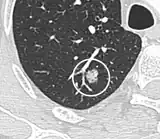

- Margin morphology: a spiculated margin is a risk factor for cancer.[8] Benign causes tend to have a well defined border, whereas lobulated lesions or those with an irregular margin extending into the neighbouring tissue tend to be malignant.[10] In particular, spiculations are highly predictive of malignancy with a positive predictive value up to 90%.[9] Also, a "notch sign", which is an abrupt indentation of the nodule, increases the risk of cancer, but may also be found in granulomatous diseases.[9]

-

subpleural nodule.[9] -

Round well-delineated solid lung nodule with smooth border.[9] -

Lobulated nodule.[9] -

Spiculated lung nodule.[9] -

A "notch sign".[9] -

A triangular perifissural node can be diagnosed as a benign lymph node.[9]